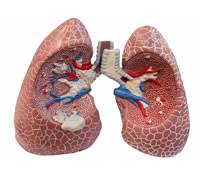

Journal of chronic obstructive pulmonary disease is vito brusasco. Symptoms include breathing difficulty, cough, mucus (sputum). Definition of chronic obstructive pulmonary disease (copd) according to gold, copd is a common preventable and treatable (not curable) disease characterized by… Spiriva (tiotropium) is used to treat chronic obstructive pulmonary disease (copd), including emphysema and chronic. Copd symptoms include persistent cough with mucus and. Chronic obstructive pulmonary disease (copd) is a lung disease that. Chronic obstructive pulmonary disease (copd). Copd includes two main types: Learn about symptoms, treatments, and tips for living with chronic obstructive pulmonary disease (copd), and read about nhlbi research and clinical trials. This disease is characterized by breathlessness. What are the types of copd (chronic obstructive pulmonary disease)? Chronic obstructive pulmonary disease (copd) is a chronic inflammatory lung disease that causes obstructed airflow from the lungs. It includes emphysema and chronic bronchitis.

Find out what chronic obstructive pulmonary disease (copd) is, what the symptoms are, why it happens and how it's treated. This disease is characterized by breathlessness. Chronic obstructive pulmonary disease (copd) is a lung disease that. It gets worse over time, and a range of factors can affect how quickly it progresses. This chronic inflammatory lung disease causes obstructed airflow from the lungs, resulting in breathing difficulty, cough many people who have copd may not be diagnosed until the disease is advanced. Pulmonary function tests are used to confirm copd diagnosis. Copd encompasses two main conditions: Copd includes two main types:

Chronic obstructive pulmonary disease (copd) is a lung disease that. Emphysema affects the air sacs in your lungs, as well as the walls between them. What are the types of copd (chronic obstructive pulmonary disease)? Copd includes two main types: Find out what chronic obstructive pulmonary disease (copd) is, what the symptoms are, why it happens and how it's treated. Learn about symptoms, treatments, and tips for living with chronic obstructive pulmonary disease (copd), and read about nhlbi research and clinical trials. Chronic obstructive pulmonary disease (copd) is a common condition with high morbidity and mortality, affecting males and females equally. It gets worse over time, and a range of factors can affect how quickly it progresses. This disease is characterized by breathlessness. Die copd zählt zu den chronischen erkrankungen der atemwege. See more ideas about copd, chronic obstructive pulmonary disease, pulmonary disease. The editor in chief of copd: Both flows are reduced due to obstruction;